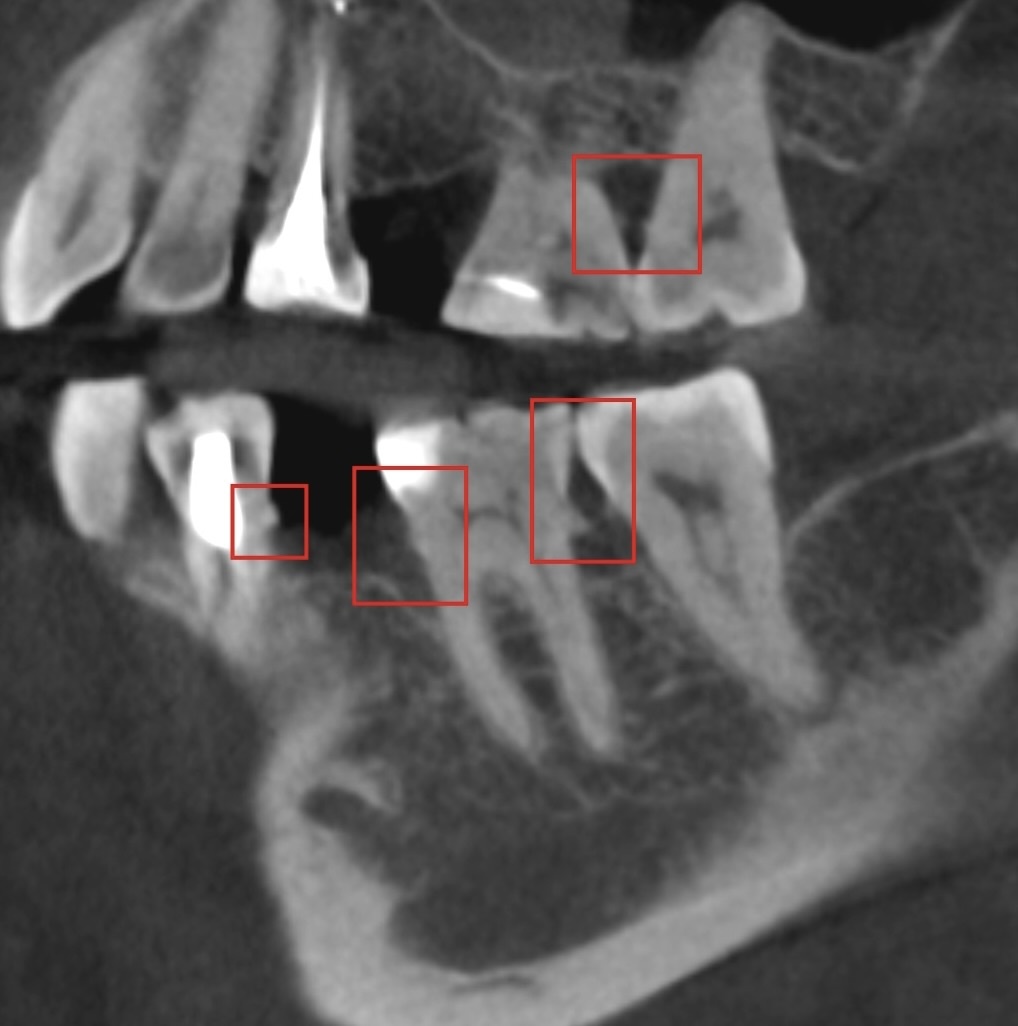

На снимке видно корни, а между ними - острые, довольно ровные “шипики”.

Это не анатомия коня такая, это и есть

минерализованный камень.

Если они видны на КТ, значит, плотность у них сопоставима с плотностью корня.

А вокруг этого плотного остова всегда есть более мягкие отложения, которые томограф, пока что, не видит. Но это вопрос времени.

Камни не обязательно проявляют себя ярко, иногда они сглажены визуально. Но они точно заметны, на корнях не должно быть наростов: